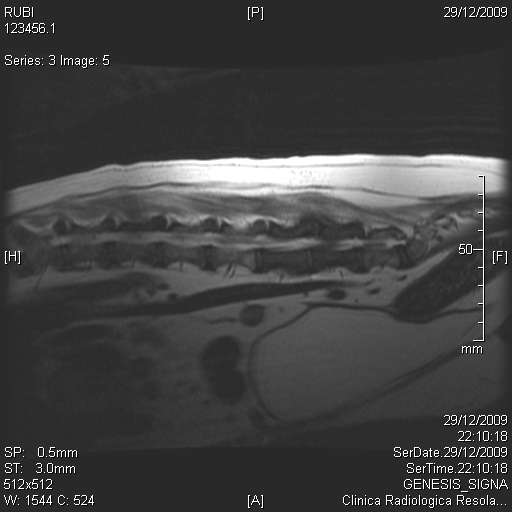

Rubi, Cocker de 8 años, llega referida al hospital por debilidad posterior y dolor intenso.La exploración neurológica revela perdida propioceptiva moderada de la extremidad posterior izquierda así como reflejo flexor incompleto izquierdo.

El estudio mielográfico es normal, pero se aprecia zona de opacidad radiológica débil en zona ventral L5-L6.

En la resonancia magnética, realizada unos días después, se aprecian ambos cuerpos vertebrales con imagen diferente así como atrapamiento de raiz nerviosa L5 por material neoformación. La imagen es compatible con osteosarcoma.

Los dueños deciden realizar cirugía para confirmar sospechas y liberar el atrapamiento. Se realiza amplia hemilaminectomía izquierda a ese nivel y se libera la raiz nerviosa L5.

El diagnóstico histopatológico del material retirada fue osteosarcoma vertebral de tipo epitelioide.

La evolución a corto plazo de Rubi fue muy buena, recuperando todas las funciones neurológicas pero 5 meses después, la situación empeoró hasta hacerse insostenible y se decidió la eutanasia.

Se presenta el estudio radiológico mielográfico y de resonancia magnética del caso